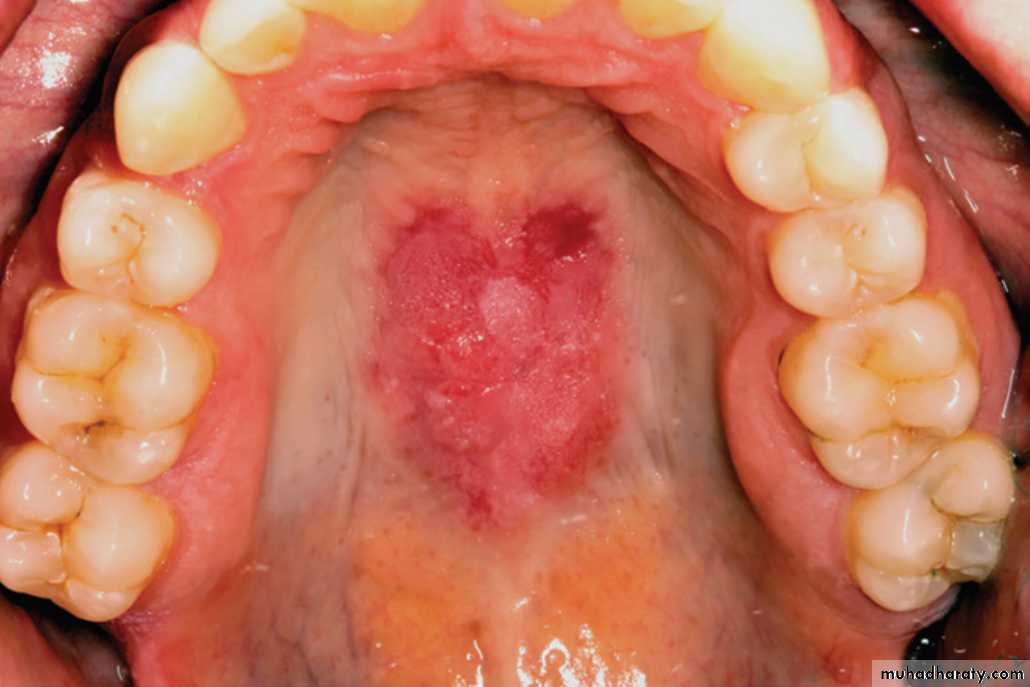

Oral lesions of LE

LE. Lesion showing a mixed red and white plaque involving the mid-posterior hard palate.•